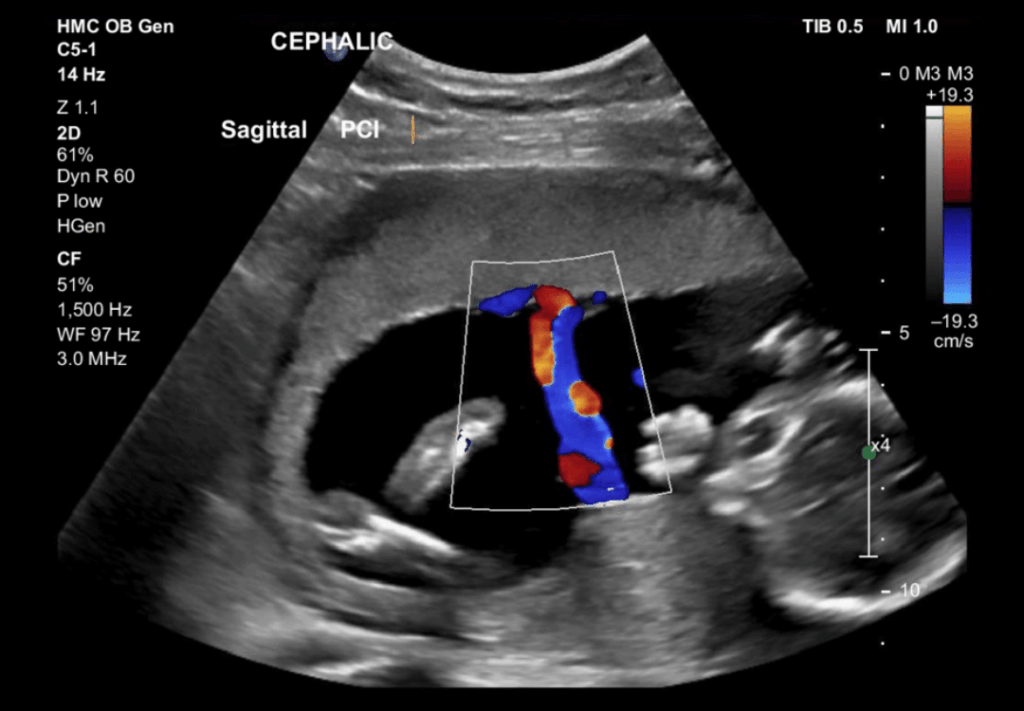

This third-trimester ultrasound monitors the baby’s growth and overall health, including: